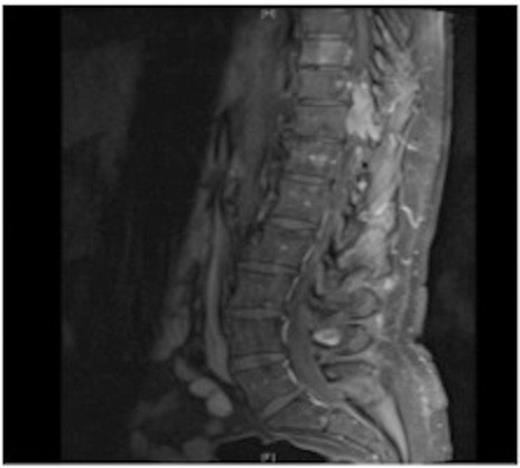

MRI showing the T10-11 extra-dural tumour with erosion of the T12 pedicle